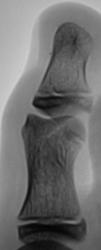

Травма. Пациент направлен врачом хирургом на рентгенографию переднего отдела стопы. Произведено исследование. Интерес у нас вызвал 1 палец. Какие мнения будут уважаемые коллеги?

Настолько качественная рентгенограмма, что передний край суставной поверхности дистального эпифиза средней фаланги первого пальца, который имеет форму буквы V, симулирует линию перелома...

это не перелом?

Я бы не исключила перелом, только не средней, а основной фаланги, средней то у первого пальца нет.